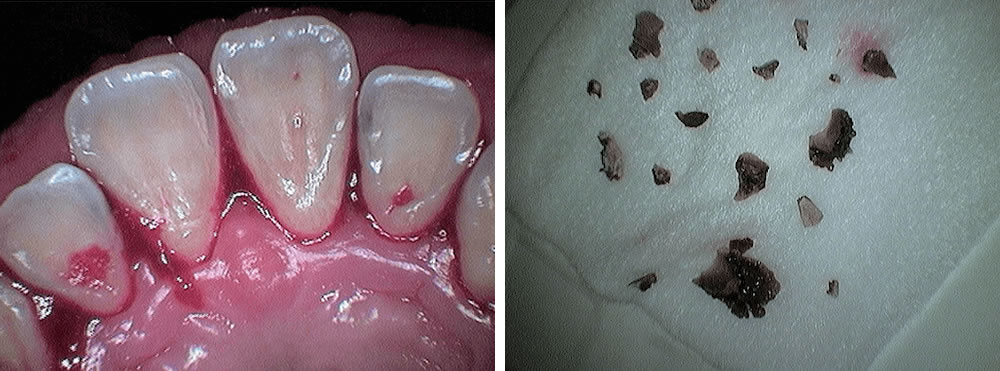

治療完了から3週間後の口腔内

治療から約3週間後。歯肉の炎症が引き、歯肉全体が引き締まっています。腫れが引いた分やや歯肉が退縮しましたが、知覚過敏はありません。 細菌検査も基準値内に改善、歯周ポケットもほぼ3㎜以下になり、患者様にも大変喜んでいただきました。